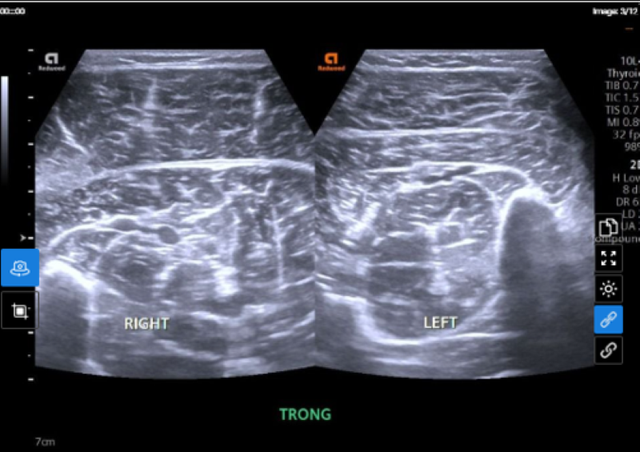

Bất thường tại chân phải được phát hiện trên hình ảnh siêu âm phần mềm. Ảnh: BVCC

Xét nghiệm virus test nhanh (5 tác nhân) cho kết quả dương tính với cúm A. Đặc biệt, trên hình ảnh siêu âm phần mềm chân phải phát hiện tình trạng phù nề cơ bụng chân trong - ngoài, cơ dép chân phải. Kết quả xét nghiệm men cơ CK total đạt 2419.6 U/L, gấp gần 60 lần mức bình thường. Chẩn đoán xác định, bệnh nhân mắc cúm A có tổn thương tiêu cơ vân cấp.